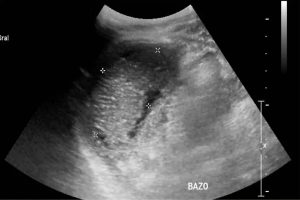

Diplomados en Ultrasonografía